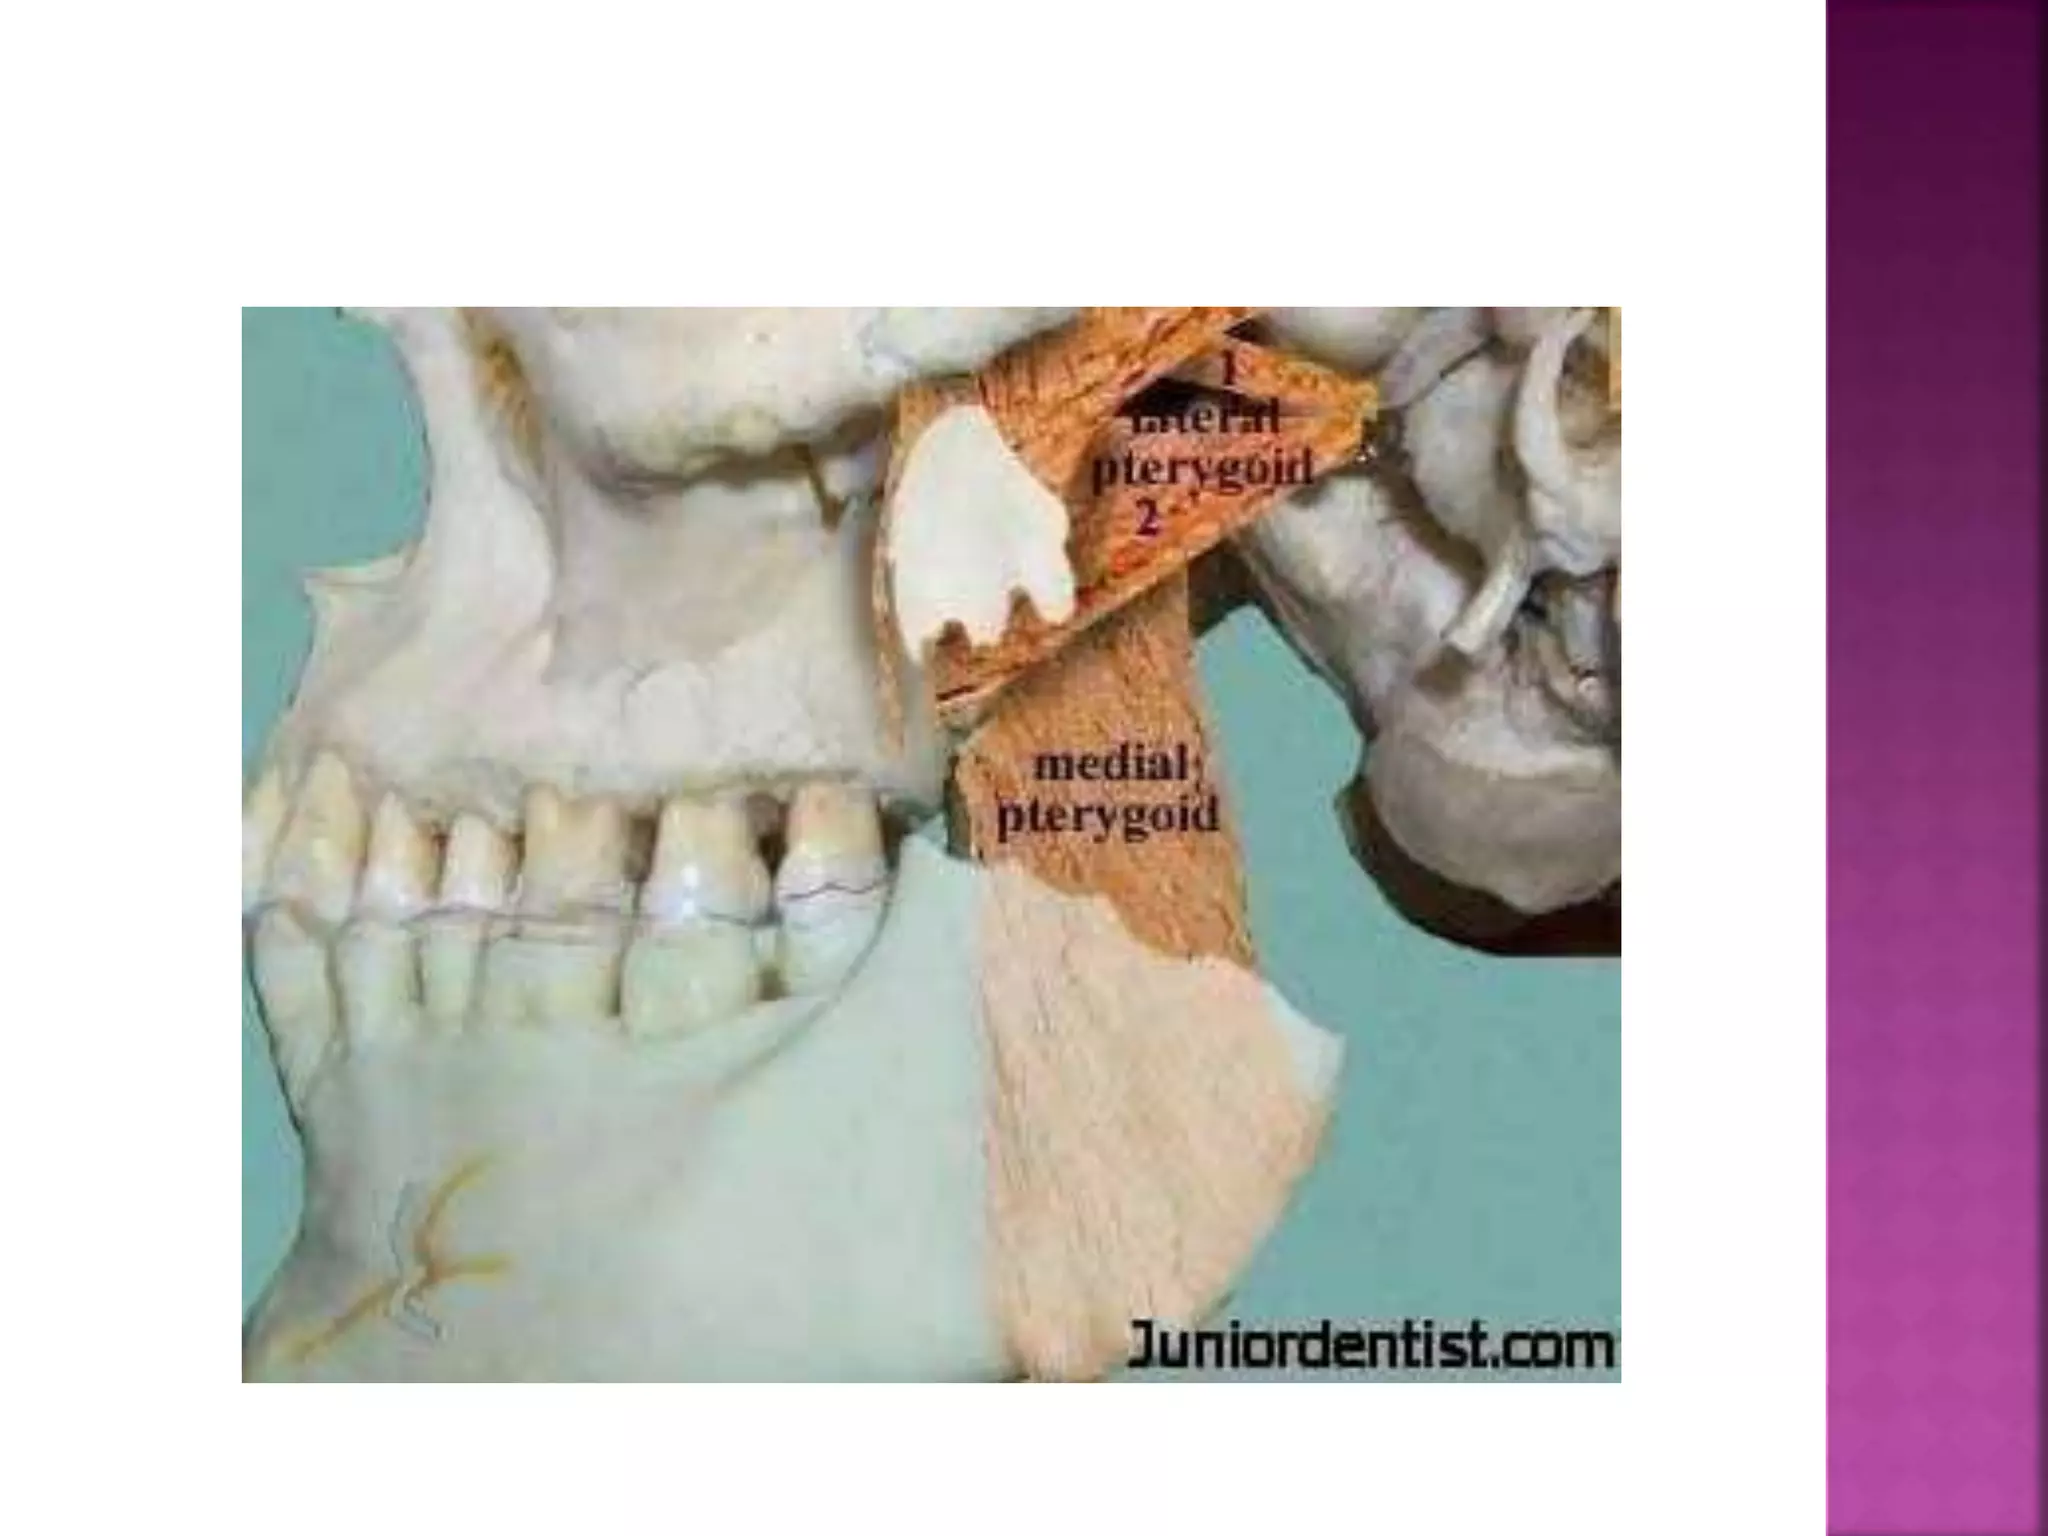

The medial pterygoid : elevates mandible, closes

jaw, helps lateral pterygoids in moving the jaw

from side to side.

 Muscle that depress the mandible:

The lateral pterygoid : depresses mandible

Three of the muscles of mastcation (temporalis , masseter and

medial pterygoid ) support the mandible against gravity and the

action of the submandibular muscles . The former exert an upward

pull and the latter downward pull.

The medial pterygoid runs from the medial surface of the lateral pterygoid plate and the palatine bone to the lower edge of

the medial surface of the ramus of the mandible.

The lateral pterygoid attaches to the lateral surface of the lateral pterygoid plate and the greater wing of the sphenoid bone.

It runs to the pterygoid fovea at the neck of the mandible and the capsule of the temperomandibular joint.